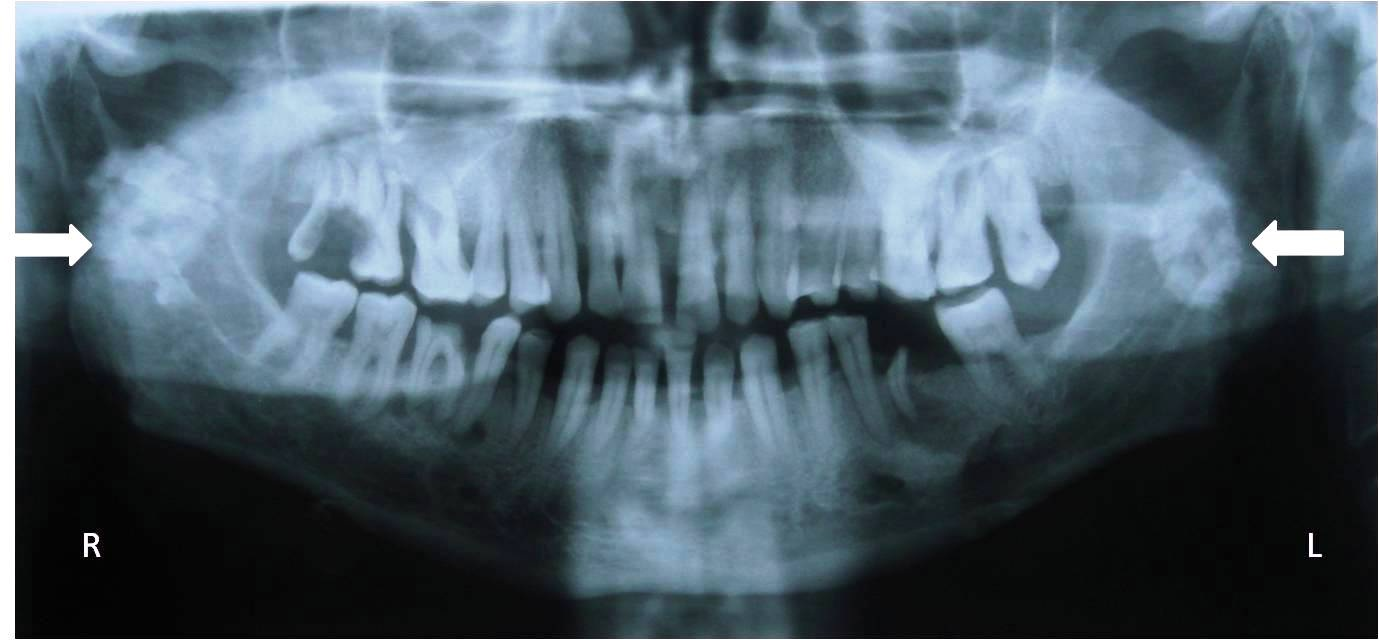

4. What condition can be seen in the following X ray?